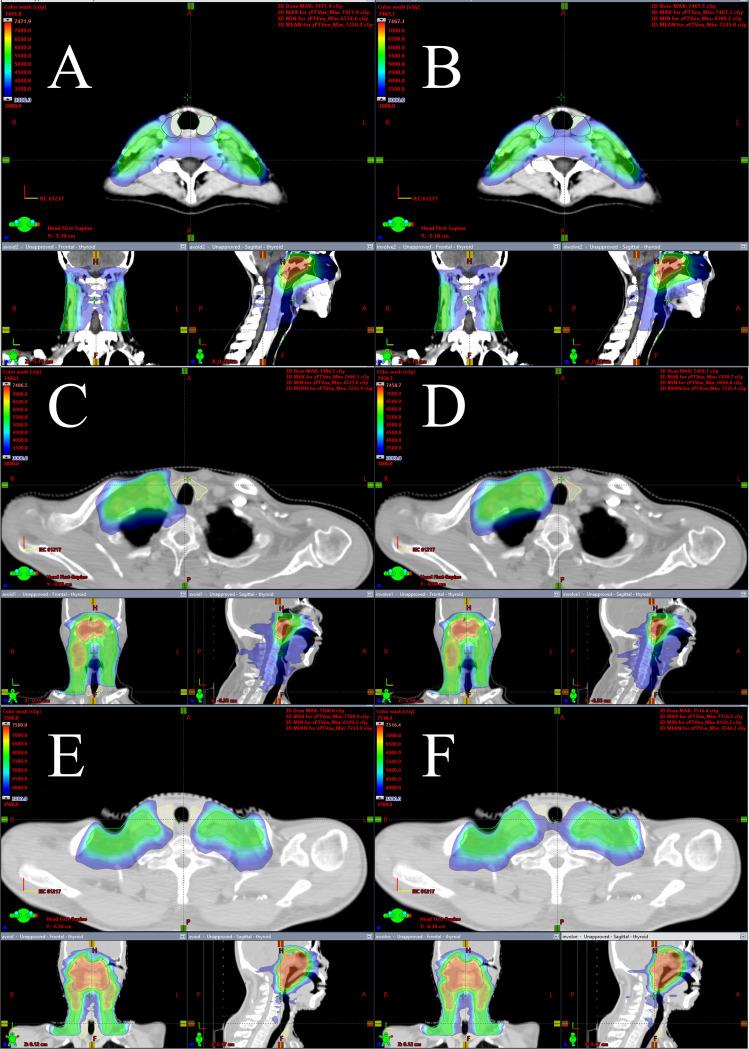

TS VMAT plans and non-thyroid-sparing volume-modulated arc therapy (NTS VMAT) plans were created using inverse-planning VMAT and computed tomography datasets of 60 patients from two centers using the Eclipse version 15.6 treatment planning system. These patients were split up into three groups, each consisting of ten patients: the bilateral upper neck irradiation group, the one-side lower neck irradiation group, and the bilateral lower neck irradiation group. Dose volume histograms, the homogeneity index (HI), conformity index (CI), and irradiation doses to the thyroid and other OARs were used to assess the two treatment plans.

There were no statistically significant differences in HI, CI, and dosage distribution to OARs between the two plans, except for the bilateral lower neck irradiation group, where mild but clinically acceptable differences were observed. Surprisingly, the TS VMAT plans significantly reduced the radiation dose to the thyroid gland across all three groups without compromising target coverage, conformity, or dose homogeneity. Specifically, the mean dose to the thyroid was substantially lower in the TS VMAT plans compared to the NTS VMAT plans. Additionally, the volume of the thyroid irradiated with 40 Gy or more was also significantly reduced in the TS VMAT plans.

The TS VMAT plan is appropriate for radiotherapy planning in patients with non-distant metastatic nasopharyngeal carcinoma. The TS VMAT plan reduces radiation dosage to the thyroid gland compared to the NTS VMAT plan, lowering the risk of hypothyroidism without exacerbating the HI, CI, and the irradiation doses to OARs.